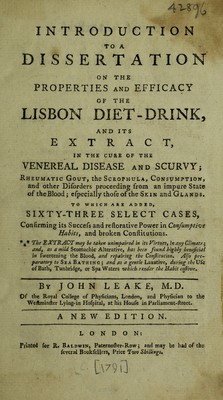

A dissertation on the properties and efficacy of the Lisbon diet-drink; a medicine ... used in Portugal, in the cure of the venereal disease and scurvy : in which, its comparative excellence with mercury and guaiacum is considered. ... Together with reflections on the improper use of mercury. ... To which is annex'd an appendix; with ... cases / [John Leake].

- Leake, John, 1729-1792

- [1780]

Credit: A dissertation on the properties and efficacy of the Lisbon diet-drink; a medicine ... used in Portugal, in the cure of the venereal disease and scurvy : in which, its comparative excellence with mercury and guaiacum is considered. ... Together with reflections on the improper use of mercury. ... To which is annex'd an appendix; with ... cases / [John Leake]. Source: Wellcome Collection.